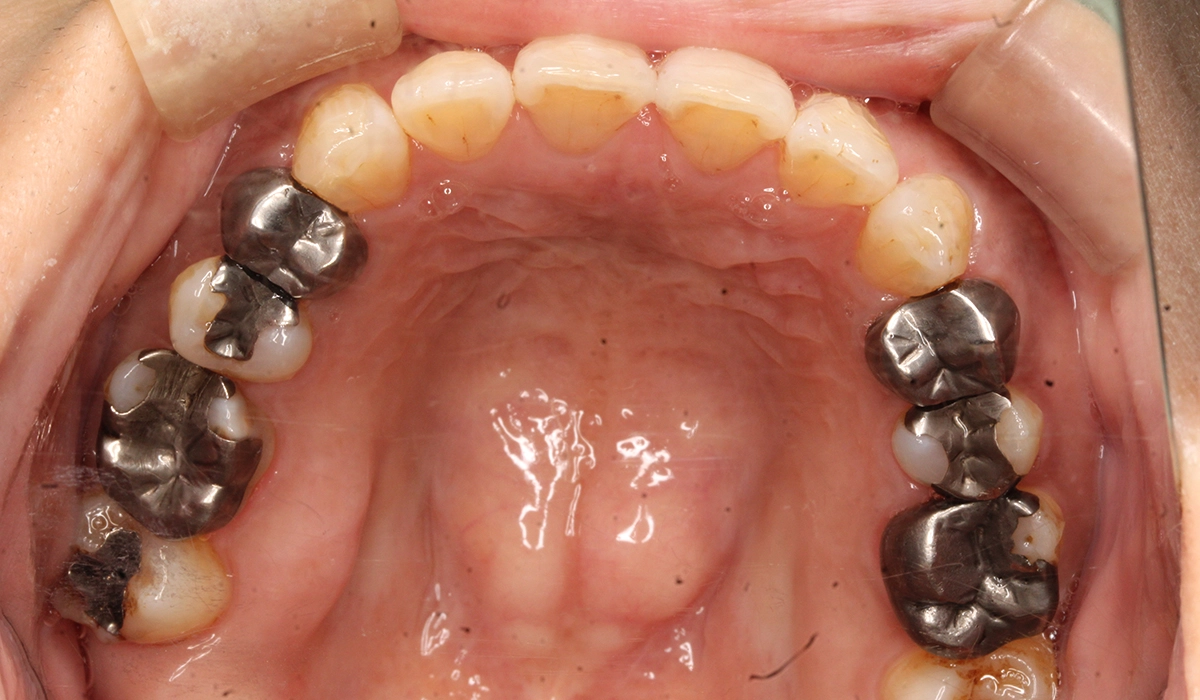

術前:下顎